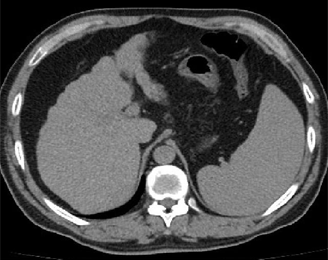

Abdominal CT showing liver cirrhosis; source: Inversitus, Wikimedia Commons.